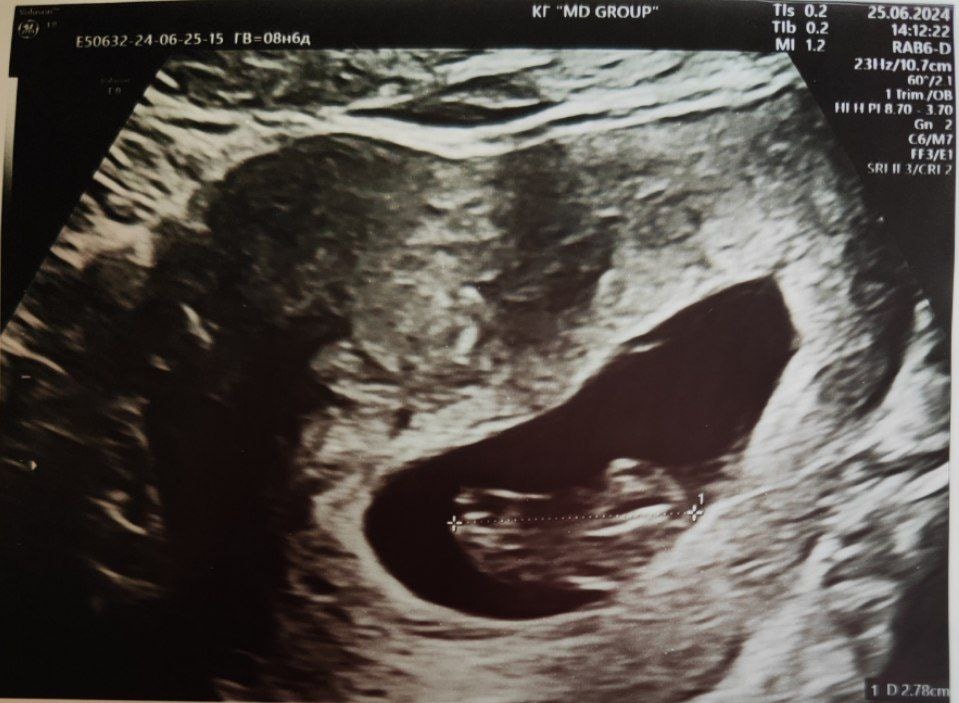

8 недель 6 дней, УЗИ для уточнения количества малышей (25.06.2024)

КТР 28мм, СБ+, один эмбрион:)